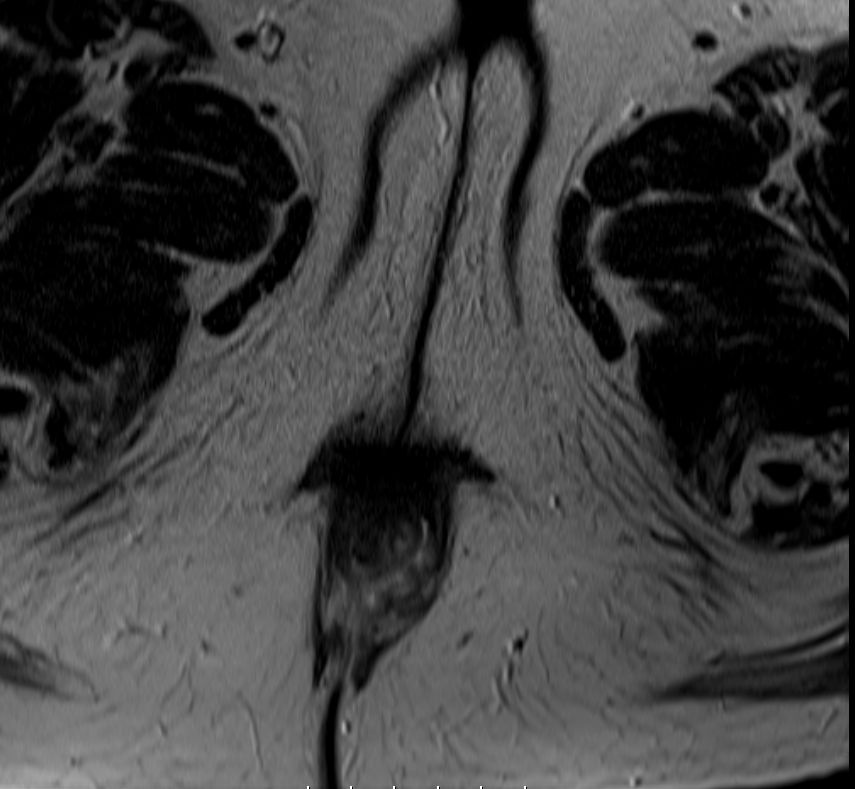

| MRT | 73-jährige Frau mit einen 1cm großen Ulkus perianal bei 5 Uhr.

Das MRT zeigt eine erhebliche Tiefenausdehnung und einen breitflächigen Kontakt mit dem Sphincter ani.